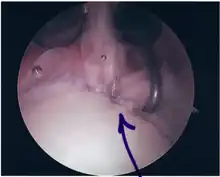

Repair of SLAP Tear

Following inspection and determination of the extent of injury, the basic labrum repair is as follows.

- The glenoid and labrum are roughened to increase contact surface area and promote re-growth.